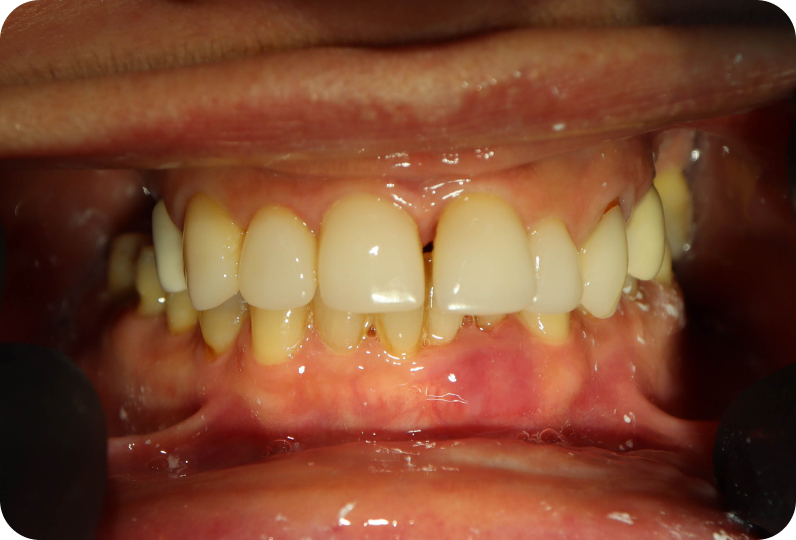

результаты

Установлен условно-съемый металлоакриловый протез на 12 зубов

Вид протеза сбоку

Спустя 7 дней на верхней челюсти зафиксирован металлоакриловый протез из 12 зубов.